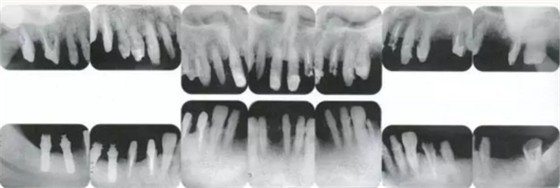

病例8

上頜前牙部前突在牙周外科處理以后得到改善的病例

▲圖16-1~3

11.png

▲圖16-4

▲圖16-1~4 56歲,女性?;加腥谘乐苎浊蚁骂M磨牙區(qū)缺失,可以看到上頜前牙區(qū)有前突的現(xiàn)象。左上1和右上1無法保留。